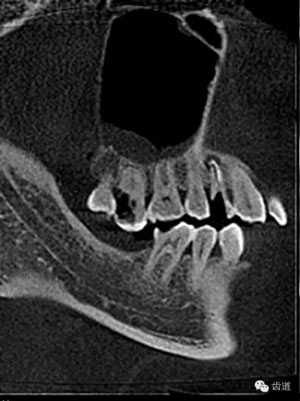

數(shù)碼攝影x片顯示:14遠(yuǎn)中鄰頜面暗影,穿髓。根尖暗影。無(wú)牙周膜增寬。

數(shù)碼x攝影顯示:近中頰根及腭根根管充填恰填,遠(yuǎn)中根管有遺漏。

檢查顯示:近頰及腭根充填恰填,遠(yuǎn)頰根管內(nèi)有少許充填物影像。根尖明顯低密度影像。